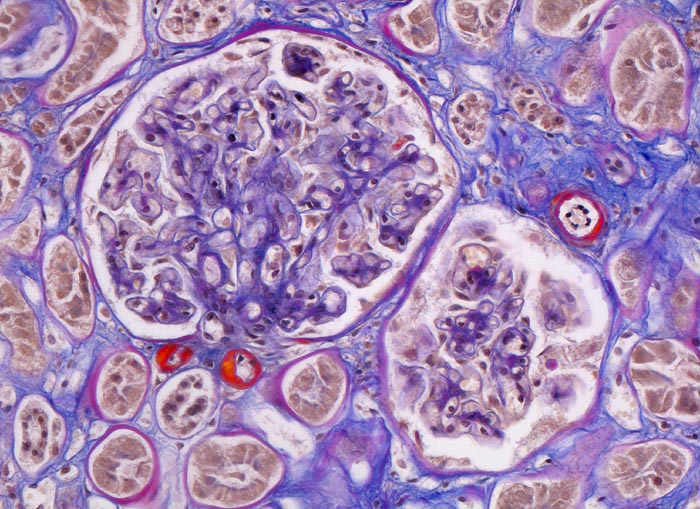

PathoPic – image database / PathoPic ID 4645 - Arteriolosklerose

Arteriolosklerose

Niere

Glomerulum mit homogenen, rotgefärbten Einlagerung in der Arteriolenwand mit Verschwinden der zellulären Gefässwandstrukturen von Vas afferens und efferens (typisch für Diabetes mellitus). Lumeneinengung der Arteriolen. Interstitielle Fibrose.

Das hyaline Material besteht aus Plasmaproteinen, Lipiden und Basalmembranmaterial. Bei arterieller Hypertonie ist in der Regel nur das Vas afferens von der Arteriolosklerose betroffen. Bei Diabetes mellitus sowohl Vas afferens als auch Vas efferens.